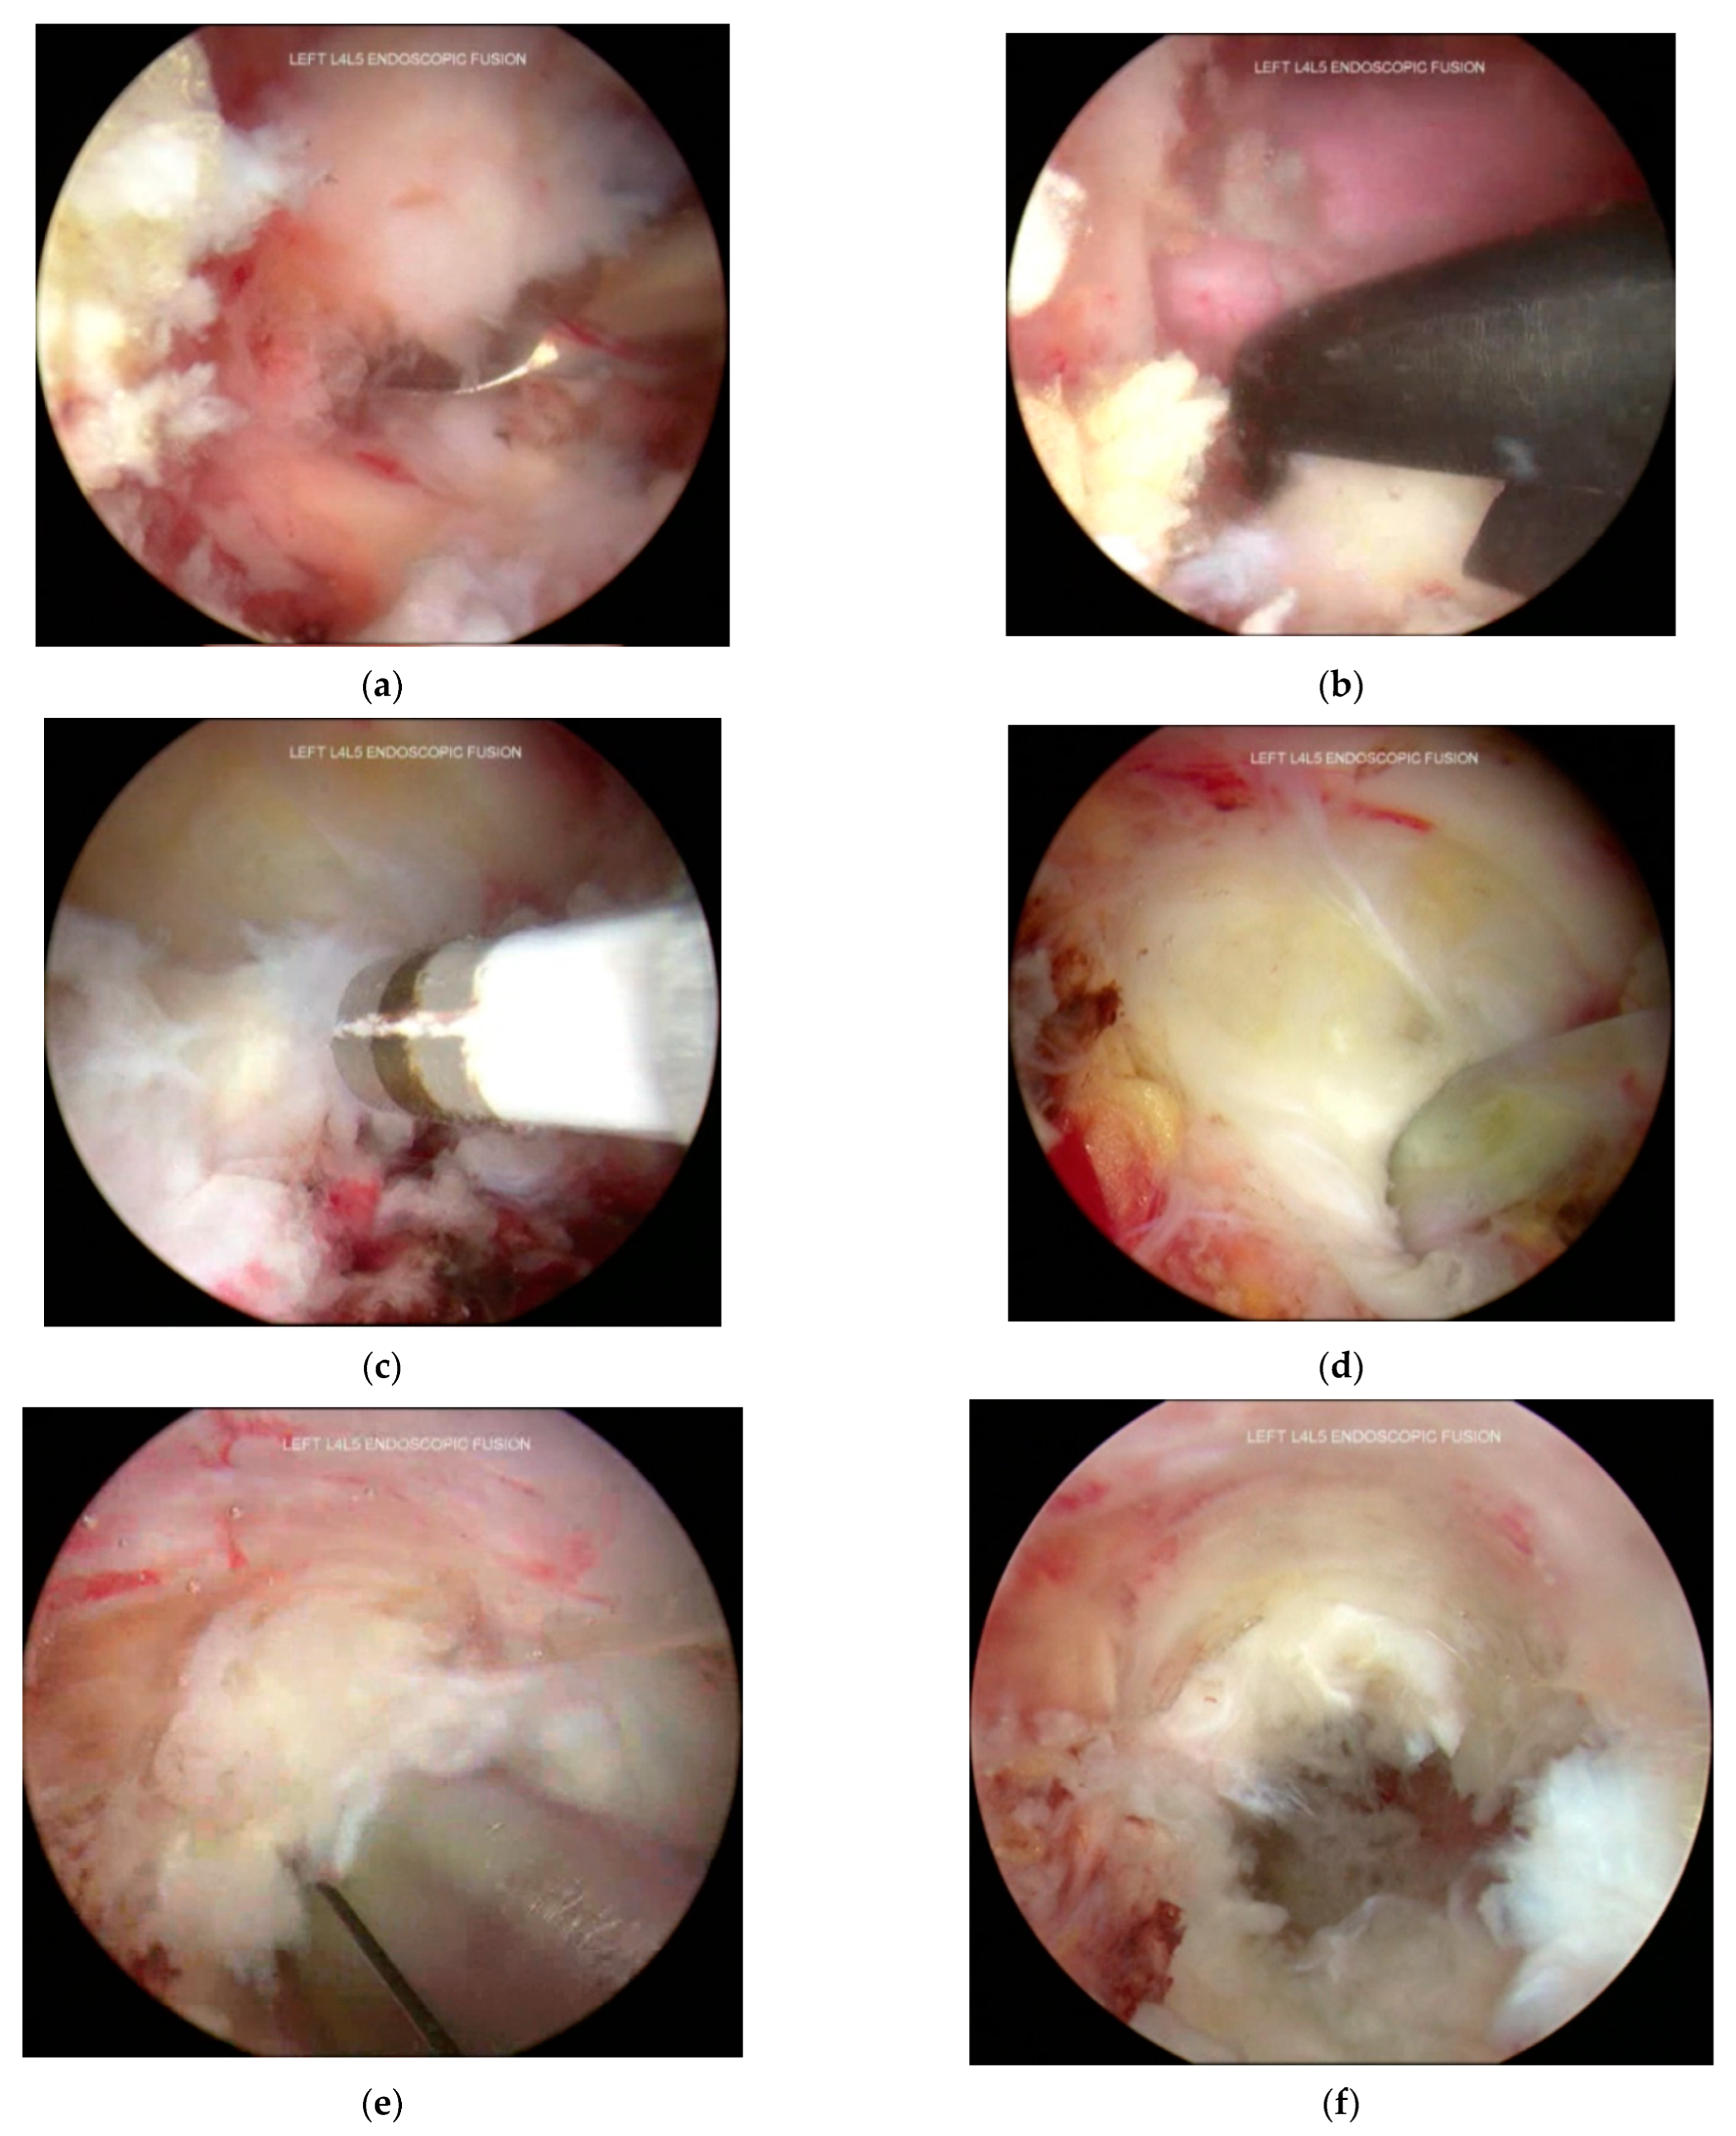

3.4. Inferior Articular Process Facetectomy

3.5. Superior Articular Process Facetectomy

3.6. Decompression and Discectomy

3.7. Endplate Preparation

3.8. Cage Insertion with Retractors